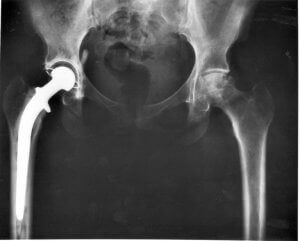

수의사가 고양이의 고관절을 살펴보고 정확한 문제를 확인하기 위해 골반 엑스레이 검사를 해야 한다. 실제로 반려묘에게 고관절 이형성증이 있다면 문제를 완화하고 증상을 늦추는 몇 가지 치료법이 있다. 안타깝게도 아직 완치할 방법은 없다.

이러한 치료법으로는 물리 치료, 특정 활동 제한, 항염증제(경구 복용 또는 주사), 체중 관찰 등이 있다. 더 심각한 사례에서는 고관절 치환술이 필요할 수도 있다.